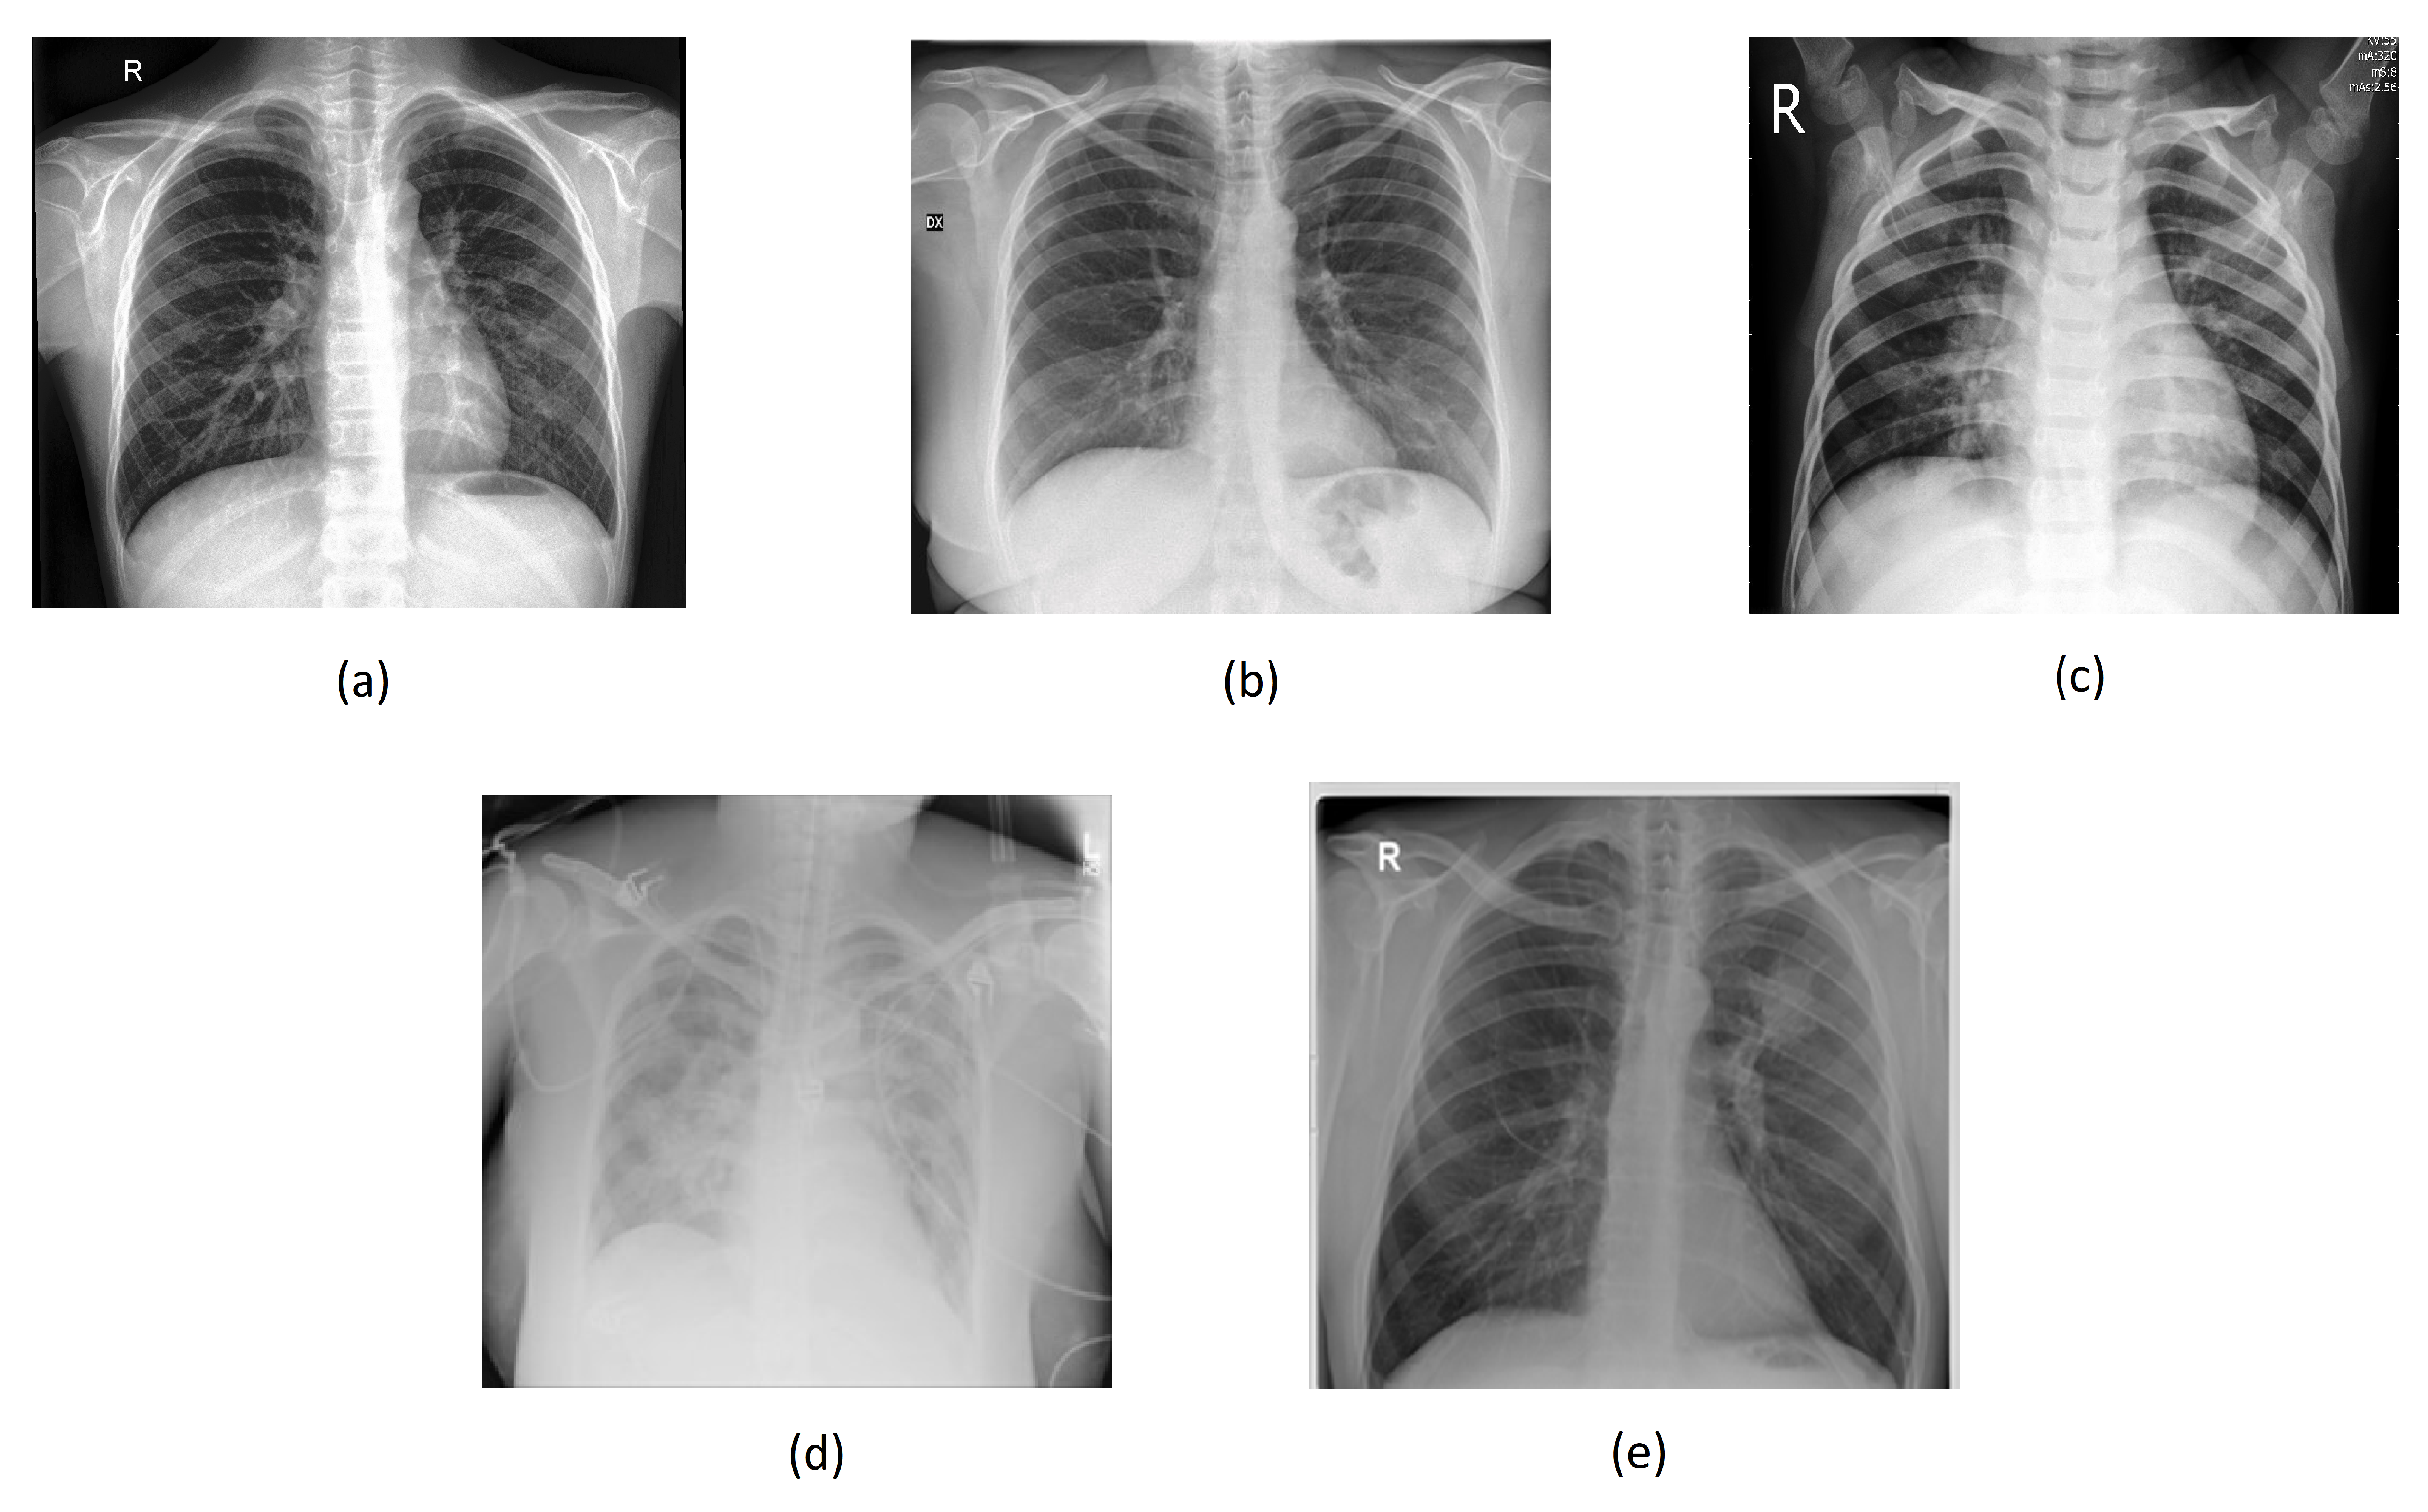

Figure 4a–e below illustrate the “normal”, “covid”, “lung_opacity”, “pneumonia”, and “tuberculosis” classes.

Figure 4. Chest images for (a) “normal”, (b) “covid”, (c) “pneumonia”, (d) “lung_opacity”, and (e) “tuberculosis” classes.